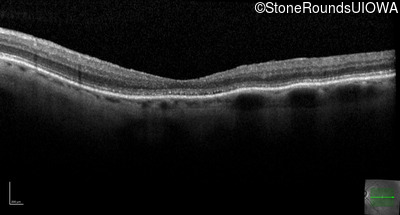

The clinical features favoring the diagnosis of RP1L1-associated occult macular dystrophy include: reduced acuity with a near-normal ophthalmoscopic appearance, a history of normal acuity in childhood; and, a "moth-eaten" appearance of the macular ellipsoid zone on OCT.

OD OS